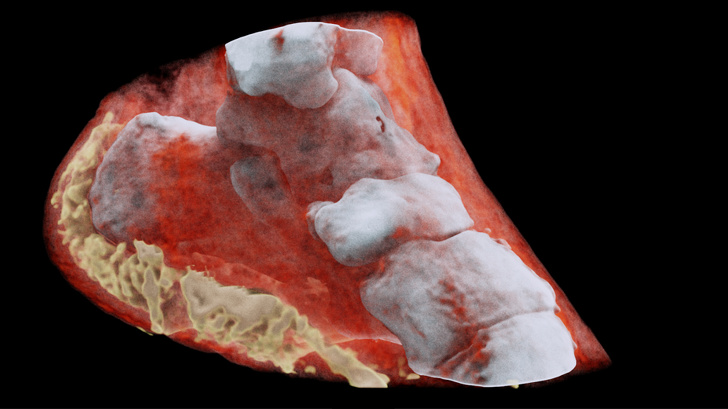

18. Так виглядають зуби людини у 7 (вгорі) і в 30 років